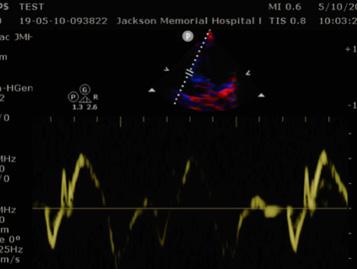

4. Tricuspid Annular Plane Systolic Excursion (TAPSE) (Fig. 2)

Significance: RV function has been shown to correlate with the RV free wall excursion, or TAPSE. Preliminary studies also suggest that the use of TAPSE in tachycardic and hypotensive patients increases the sensitivity for identifying acute PE. A normal value is >20 mm, and excursion of less than 16mm is considered abnormal, and suggestive of RV systolic dysfunction and, consequently, RV strain. Technique: The goal is to measure the movement of the tricuspid annulus from the end of diastole to the end of systole using M-mode. Step 1: Obtain the A4C view. Step 2: Place the M-mode marker through the lateral tricuspid annulus. Step 3: Measure the distance from the peak to the valley.